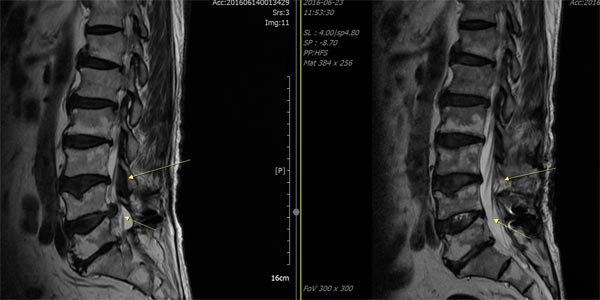

허리 디스크와는차이나게 척추관 협착증은 요통보다는 다리 저림이나 당김 증상이 있어, 보행에 제일 큰 고충을 체감할 수 있습니다. 때문에 오래 걷기가 힘들고 오래 걷지 않았음에도 자꾸 주저앉게 되는 성향이 존재하는데 표준적인 협착증의 증상이라 할 수 있습니다. 기본적으로 요추부(허리)의 문제이긴 하지만 허리디스크와 다르게 허리 통증이 한결같이 동반되지는 않으며, 있더라도 허리디스크에 대조해서 적은 정도의 통증이 일어납니다.

신경을 누를 때 신경의 지배를 받는 부위로 쑤시거나 화끈거리는 통증을 호소하게 되겠습니다. 만에 하나라도 경추부(목)에 척추관 협착증이 만들어 낸다면 상/하지 모두에 영향을 줄 수 있어 다리 근력감소, 보행 불편을 나타나게 할 수 있습니다. 요추(허리) 협착증은 방사통이 엉덩이에서 시작, 다리 아래로 하향할 수 있고 이 증상을 거의 좌골신경통이라 합니다.

척추관 협착증은 척추관의 좁아짐과 신경 구조에 압력이 가해지는 것으로 인해 많은 종류의 증상이 일어날 수 있어요. 주로 통증이 띄엄띄엄 생겨날며 허리, 목, 아니면 다리 등의 부위에서 통증이 나타날수 있습니다. 뿐 와 함께 또 저림 혹은 마비가 나타날수 있기도하고 특이하게다리에서의 저림이나 마비가 예사로 보여집니다.

심하다 못해 나중에는 족하수, 즉 발에 힘이 안입회하고 걸을 때 발이 끌리는 현상이 생기게 되겠습니다. 허리를 앞으로 숙이면, 척추관이 넓어지고 해서 허리를 숙이고 있거나 앉아있는 것이 소홀하게 느껴지고요. 허리를 펴고 오래 걷거나 서있기 어려우며 100~200m 이상 걸으면 다리에 힘이 빠지거나 통증이 심해 쪼그려 앉아서 쉬게 되겠습니다.

척추관 협착증 환자는 협착된 척추관 부근에 염증이 발생하여 심각한 통증을 느끼게 되고, 두꺼워진 인대가 신경을 압박하게 되고요. 자생한방병원에서는 염증과 부기를 가라앉히는데 효과가 있는 디스크 치료 한약으로 협착으로 인해 유발된 통증을 감량시켜주며, 부서진 근처 연조직의 흠집를 낫게 하죠. 한약은 퇴행된 뼈의 재생을 증대시키고 두꺼워진 인대 근처의 염증을 가라앉히는 효과가 있어요. 자생에서는 이런 한약과 나란히 척추관을 벌려주는 추나요법 등을 같이 진행하여 척추관 협착증을 치료하죠.